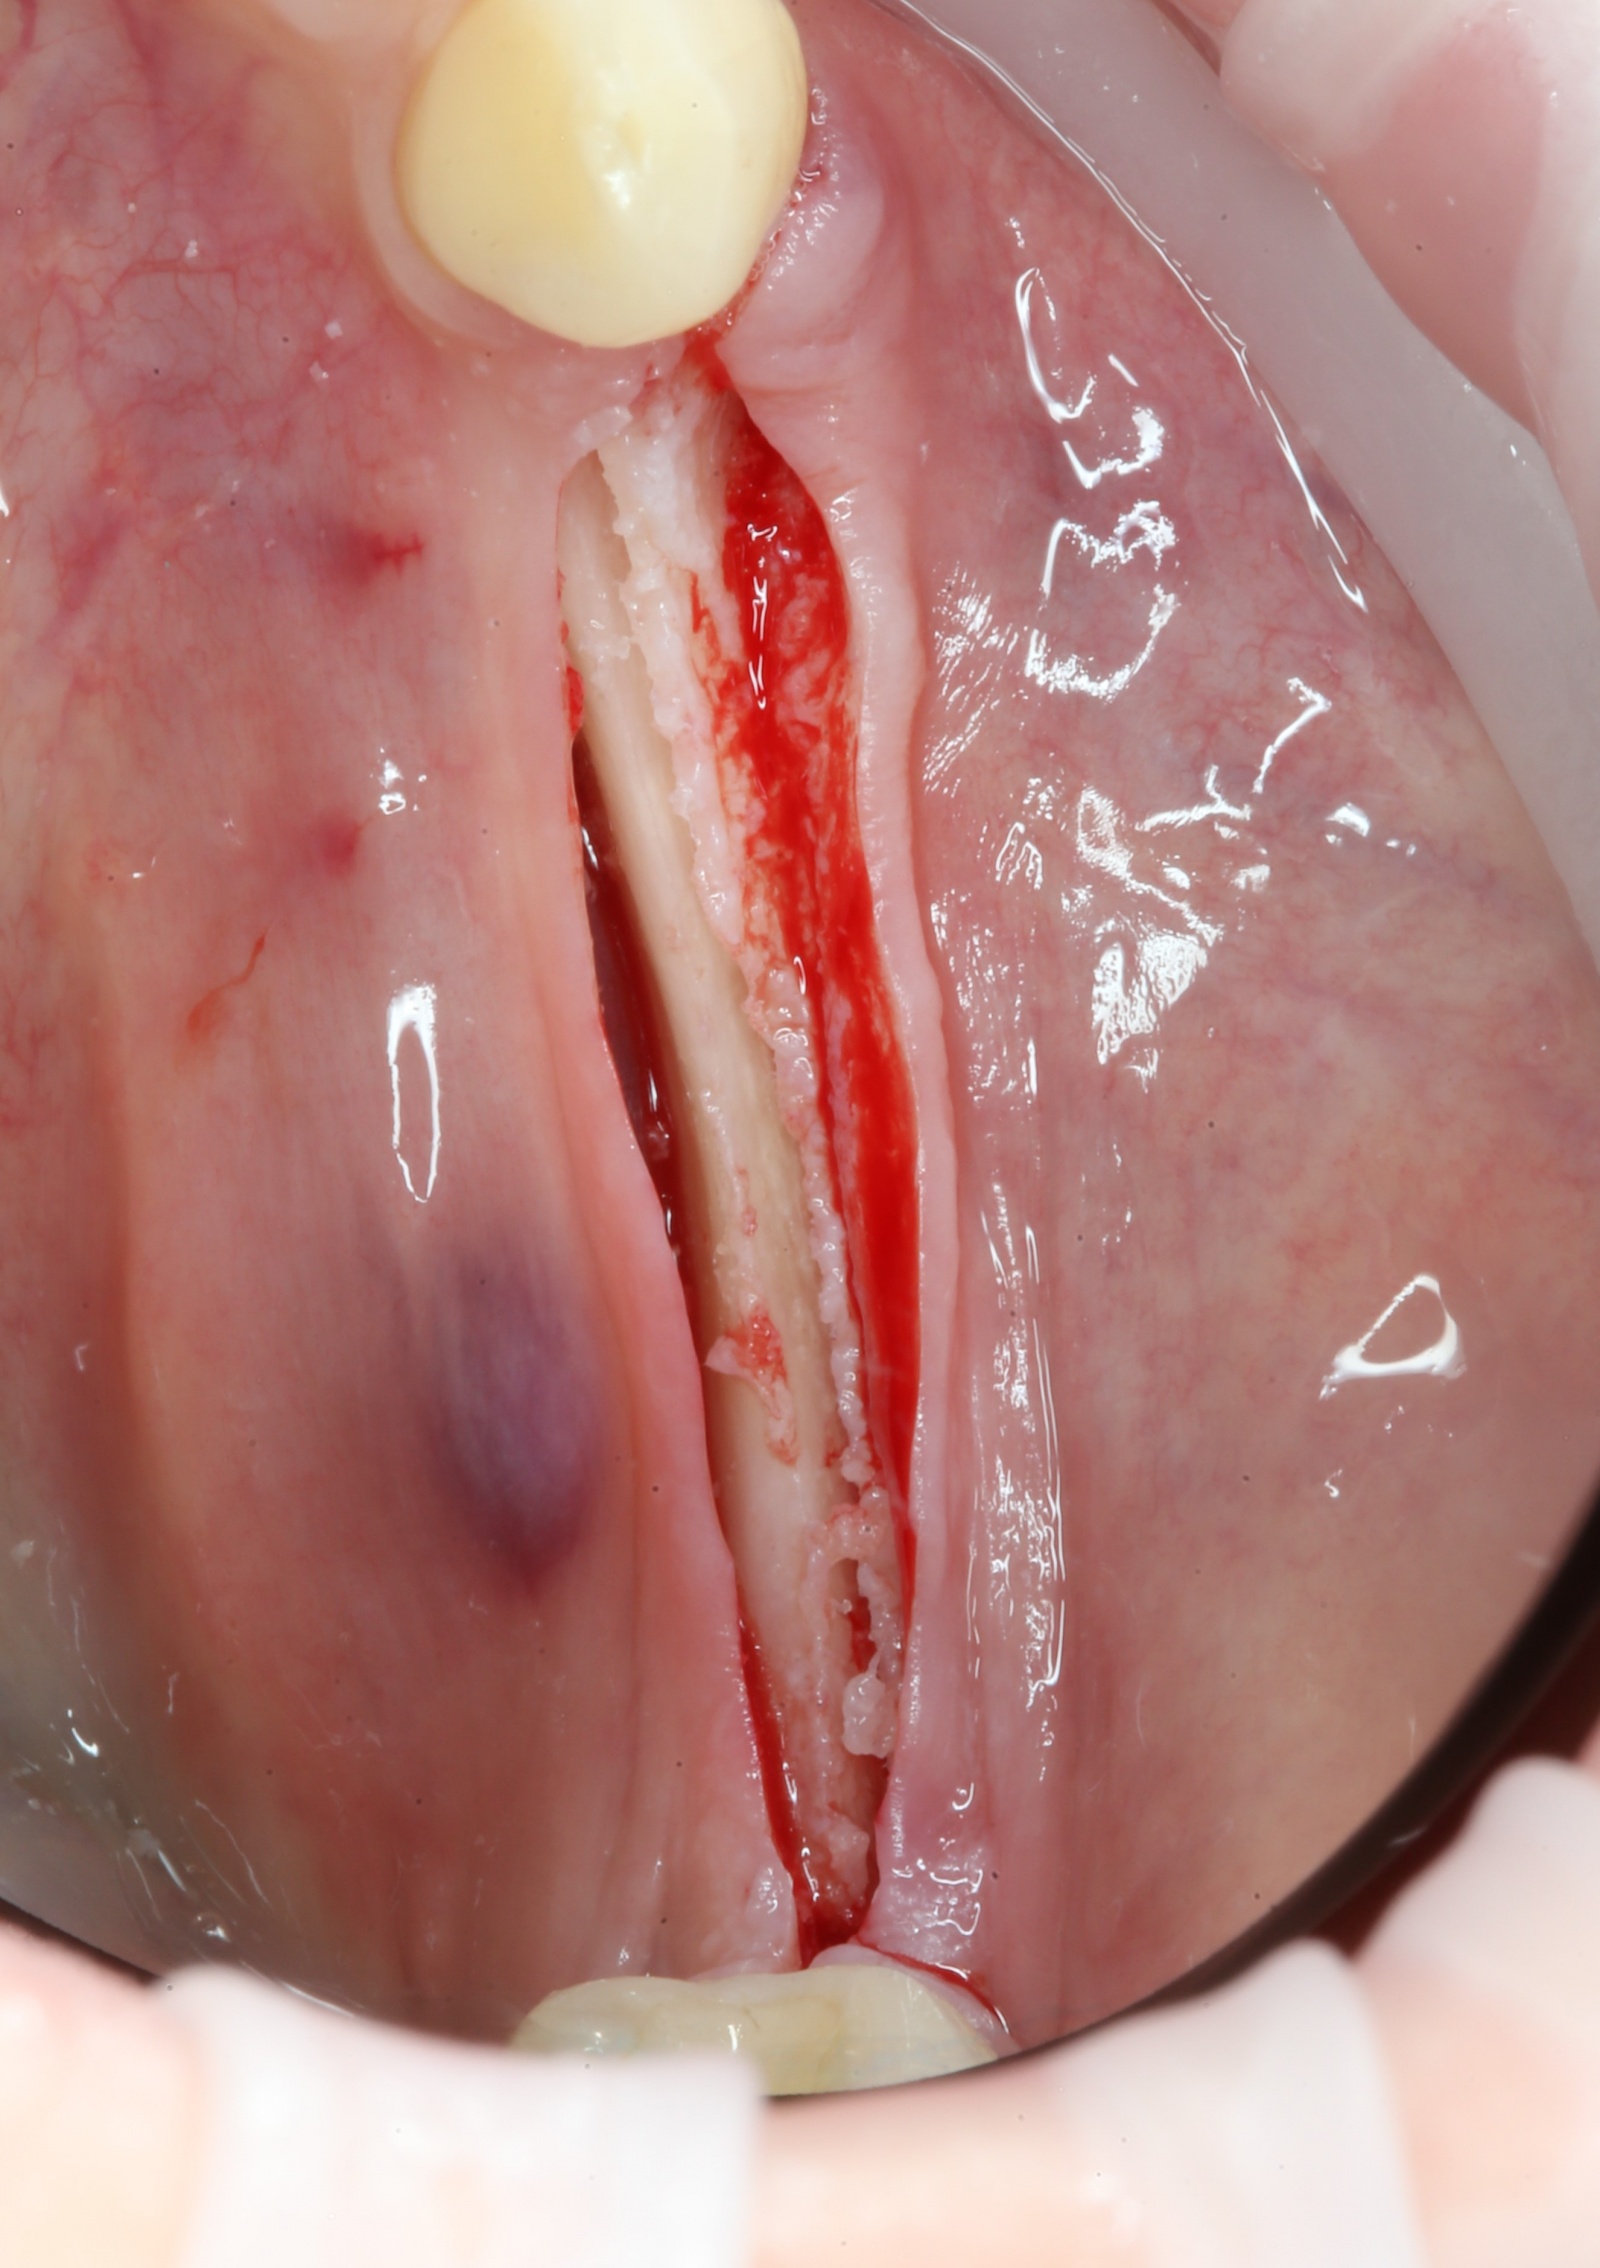

После того, как анестезия подействовала, при помощи скальпеля производится разрез, а с помощью распатора – скелетирование кости. (отделение надкостницы от компактного вещества кости).

Разрез: